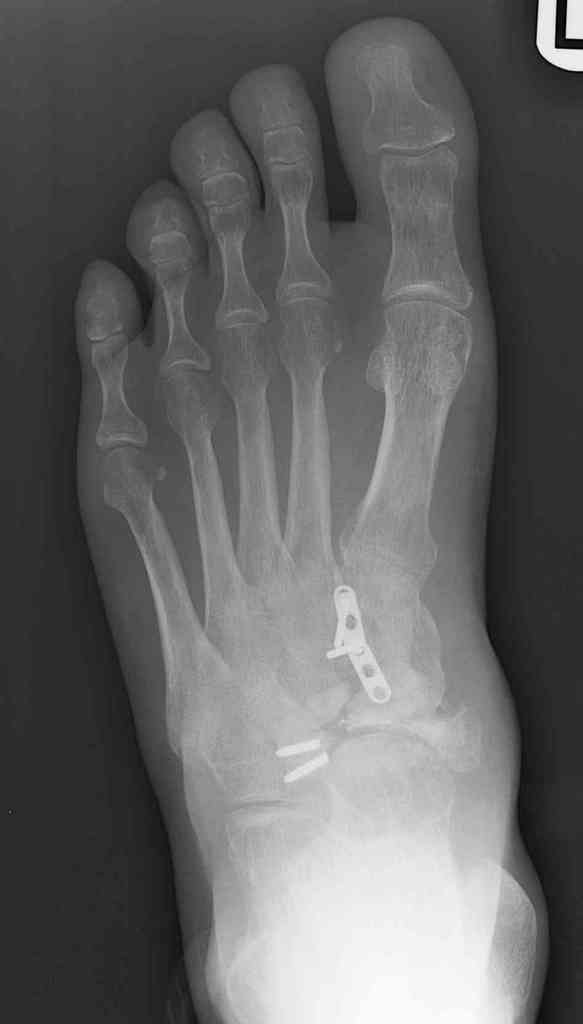

Navicular non-union

This is a 44 year old male laborer, smoker, who had his foot caught in a forklift about a year ago.

He had an ORIF and subsequent removal of hardware and presented to me with severe midfoot pain. His medial column is grossly unstable on exam but is passively correctable. Wounds are well healed, no sign of infection.

I haven't found much literature on salvage for this. What next? Iliac crest graft for structure with talo-navicular-cuneiform arthrodesis to restore the medial column? Will this fuse as an isolated procedure and given the loss of most of his subtalar motion, would a talocalcaneal arthrodesis improve his chances of fusion?